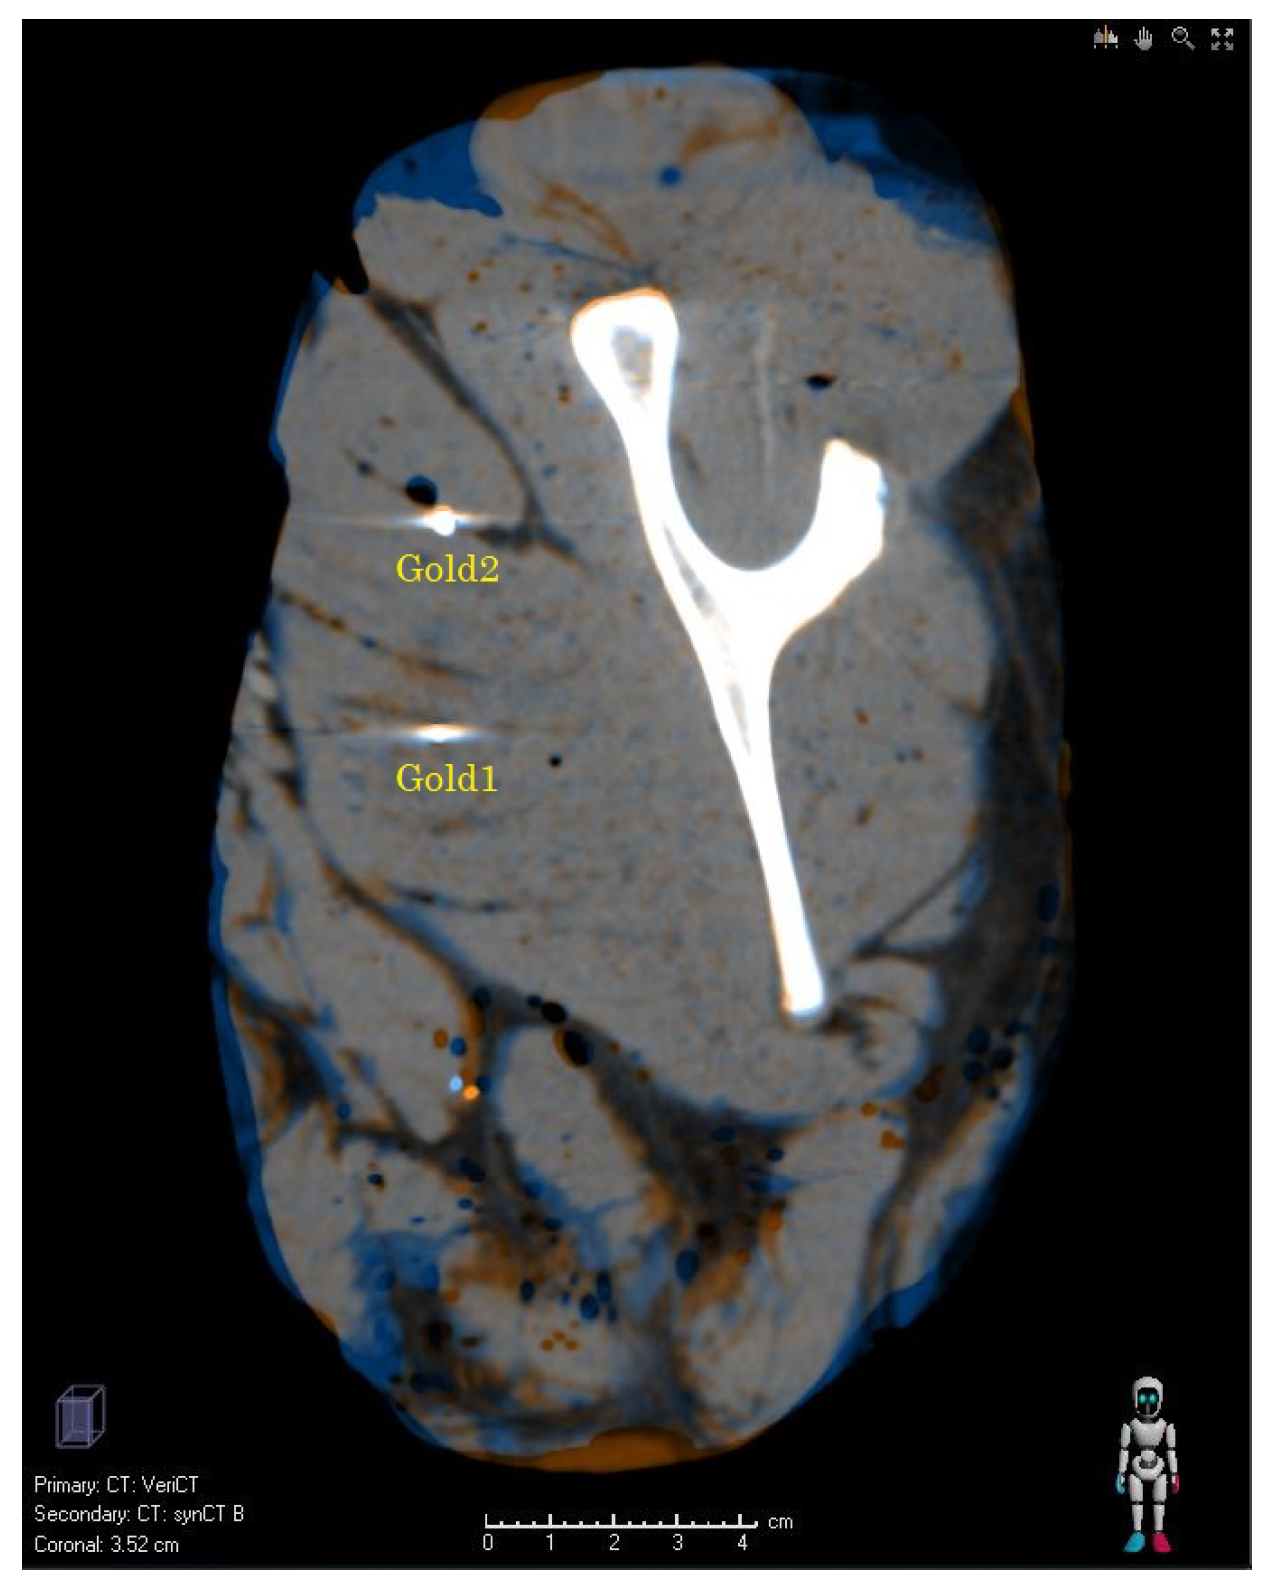

3.1. Validation of the Synthetic CTs—Results

3.2. Preliminary Results of the Clinical Study